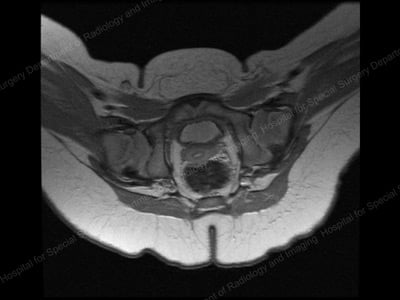

MRI image of relocated (anatomically aligned) hip.

Following closed reduction of the hip, the patient is placed into a spica body cast for 12 weeks to maintain proper alignment of the hip ball and socket. At HSS, we use cross-sectional, 3D MRI imaging of the hip after closed reduction in order to confirm appropriate location of the hip and confirm hip joint congruency. HSS prefers to use MRI imaging, rather than X-rays or CT scans, since radiation is not involved.